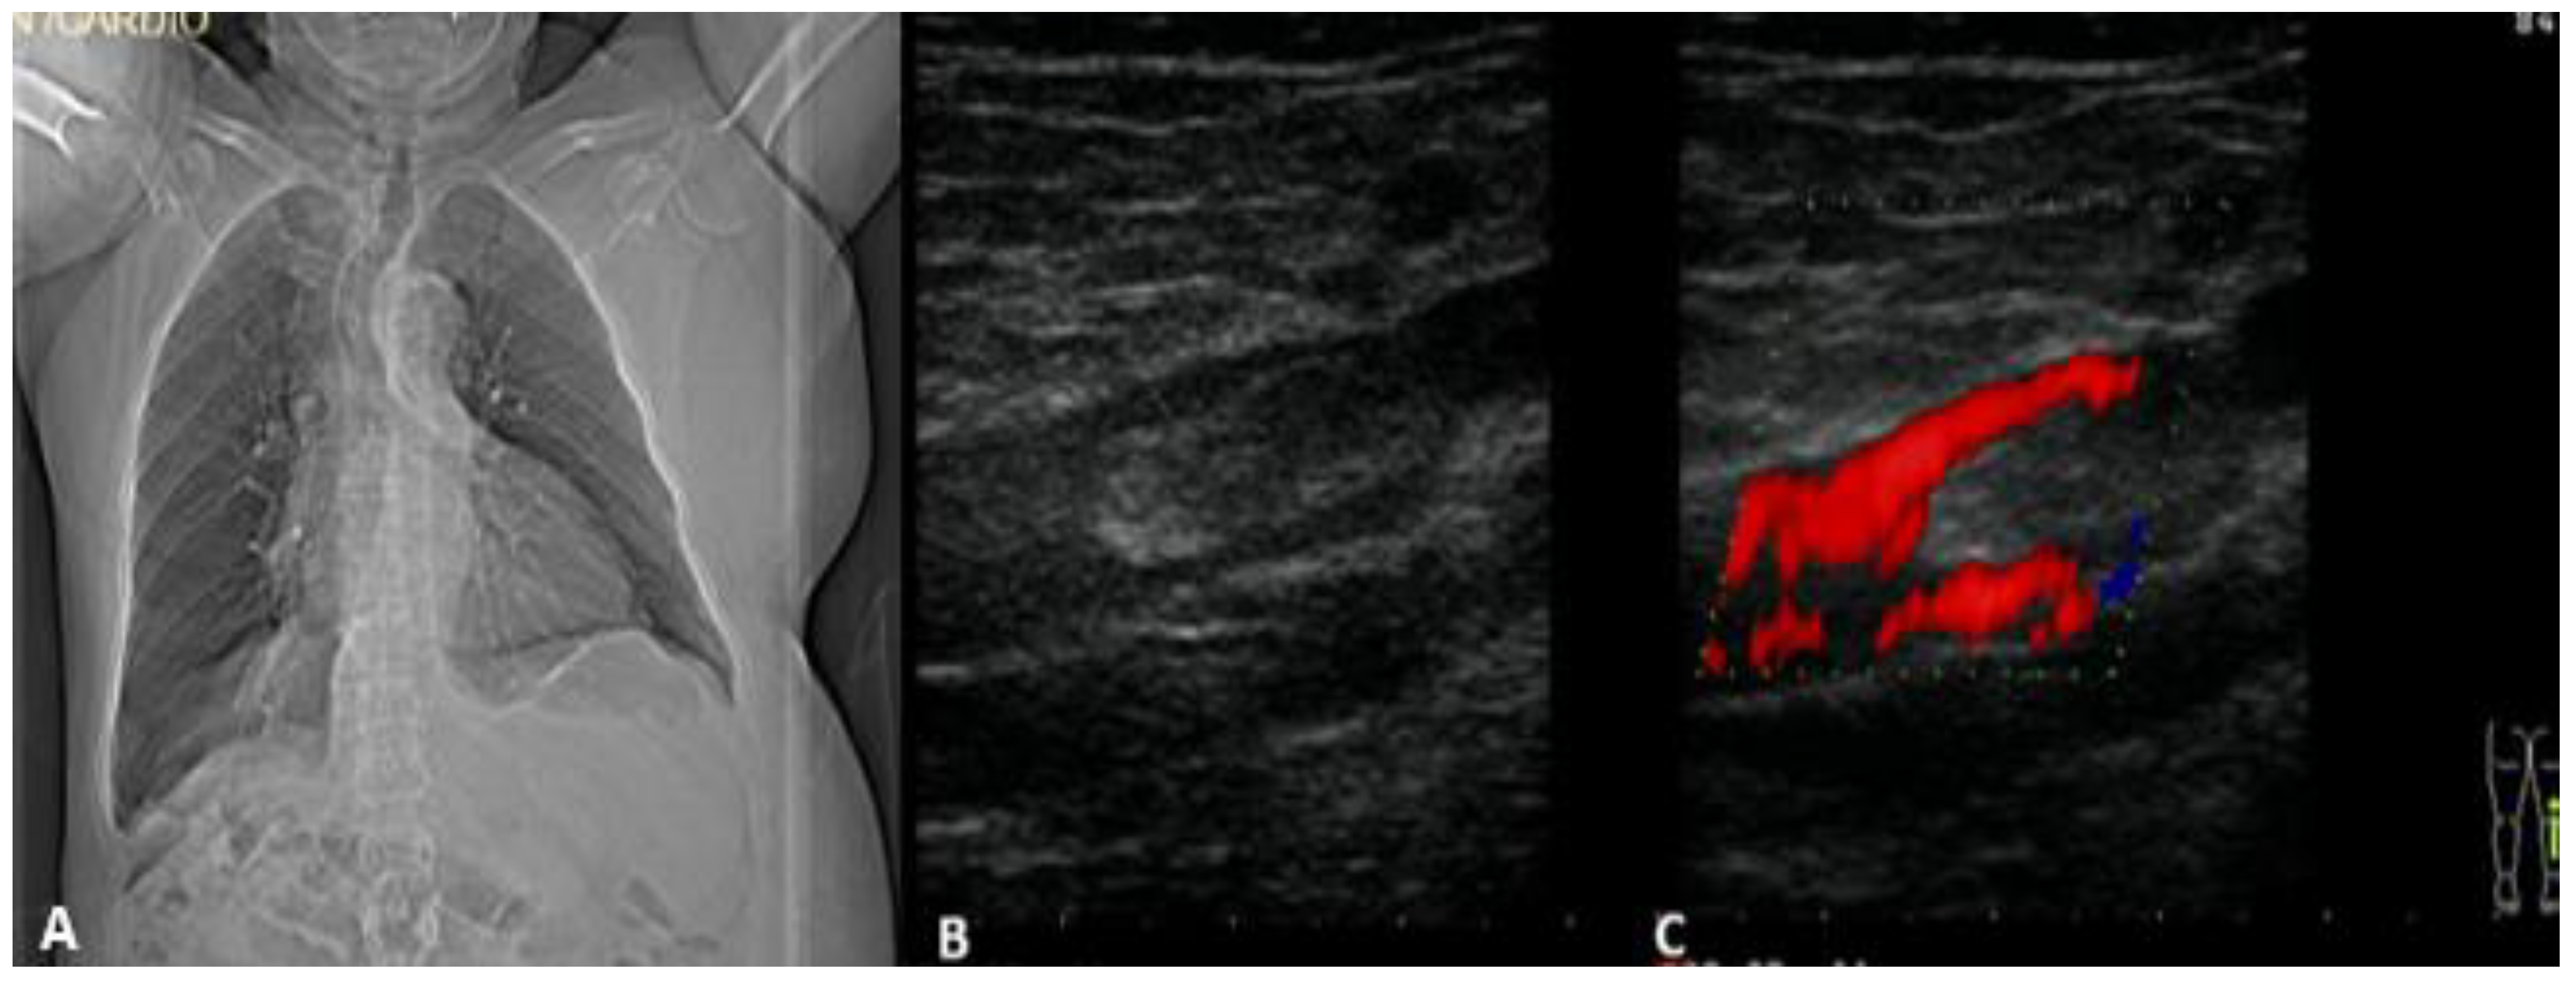

2. Case Presentation